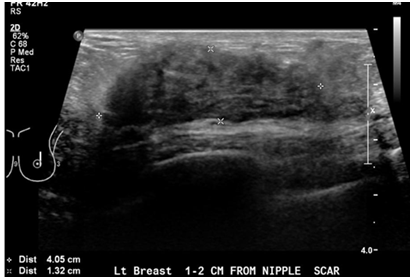

A 68year old woman was found to have an abnormal finding on routine mammography Patient has past history of type 1DM, peripheral neuropathy, hypothyroidism, HTN and a surgical biopsy left breast greater than 20years ago; with a family history of breast cancer in paternal aunt. Screening mammogram showed an apparent increased large lobular nodular density in the subareolar region deep to the nipple measuring atleast 2.5cm in the left breast. Subsequent Ultra Sound [US] of left breast showed a mass in the region of the scar site, 2cm from the nipple, measuring 41x13x46mm demonstrating some internal blood flow on Doppler. The mass was hypoechoic and slightly heterogenous with relatively circumscribed margins. Left axilla showed normal Lymph nodes [LN]. Patient underwent US-guided biopsy. Pathology showed hyalinized stromal fibrosis and chronic mastitis. This benign pathology was discordant with mammographic and sonographic imaging findings. Therefore, surgical excision was recommended with a breast surgeon follow up. Soon thereafter, patient presented with a painless palpable area of concern in the superior and subareolar Right breast of two weeks duration. Mammography and US of right breasts showed a very dense tissue in the palpable area of concern, corresponding to heterogeneous, slightly hypoechoic mass with relatively circumscribed margins measuring 38x18x65mm with internal vascularity. It had a very similar appearance to the area that was biopsied on the left breast in a similar position which demonstrated stromal fibrosis and chronic mastitis. A coarsely calcified vessel was noted running through the area of concern. No abnormal lymph nodes were detected. Given the bilaterality and history of diabetes, a preliminary diagnosis of bilateral diabetic mastopathy was made. A decision was made to follow up annually with regular mammography. In September 2017, patient developed retraction in the skin and nipple areolar complex in both breasts. Mammogram and US of both breasts revealed large densities which were relatively stable, however the skin changes prompted repeat biopsies. Thickened tissue on both breasts was excised and sent for pathology. Pathology showed collagenous stroma with keloidal features and an increased concentration of stromal spindle cells. The breast lobules revealed atrophy, infiltrated by mature small lymphocytes. A perivascular lymphocytic infiltrate was noted. The morphological features were consistent with diabetic mastopathy. The rest of the breast tissue revealed apocrine metaplasia and ductal dilatation. No atypia or malignancy was identified.

Diabetic mastopathy, also known as lymphocytic mastitis or lymphocytic mastopathy is seen occasionally in premenopausal women who have longstanding type 1 diabetes mellitus. This case underlines the importance of considering diabetic mastopathy on the list of differential diagnoses when evaluating breast lesions in a diabetic woman. Patients with DMP clinically present with painless, irregular hard unilateral or bilateral breast masses. It is rare as it represents represent 0.6% to 13% of benign lesions observed in woman with type 1 diabetes.2 Core biopsy is recommended for diagnostic confirmation. Pathology shows dense keloid-like fibrosis and periductal, lobular, or perivascular lymphocytic infiltration.3−5 The pathogenesis is not fully understood but many theories involving the effects of sustained hyperglycemia and glycosylated end products on the connective tissues of the breast have been proposed. Also it may represent an autoimmune reaction as the histologic features are similar to those seen in other autoimmune diseases.6 There are no large series with long-term follow up, but most reports recommend annual clinical and radiological monitoring and, in case of a new lesion, an additional biopsy must be considered. Once the diagnosis is established, excision is not necessary and malignant transformation has not been described. Conservative management is adequate for the majority of patients. Lesions have a tendency to recur after resection.2,7 Recognizing the presentation of this rare condition can help avoiding unnecessary surgical intervention (Figures 1 & 2).

Figure 2 Ultrasound of the breast showing mastopathy changes, 321x218mm (72x72DPI).